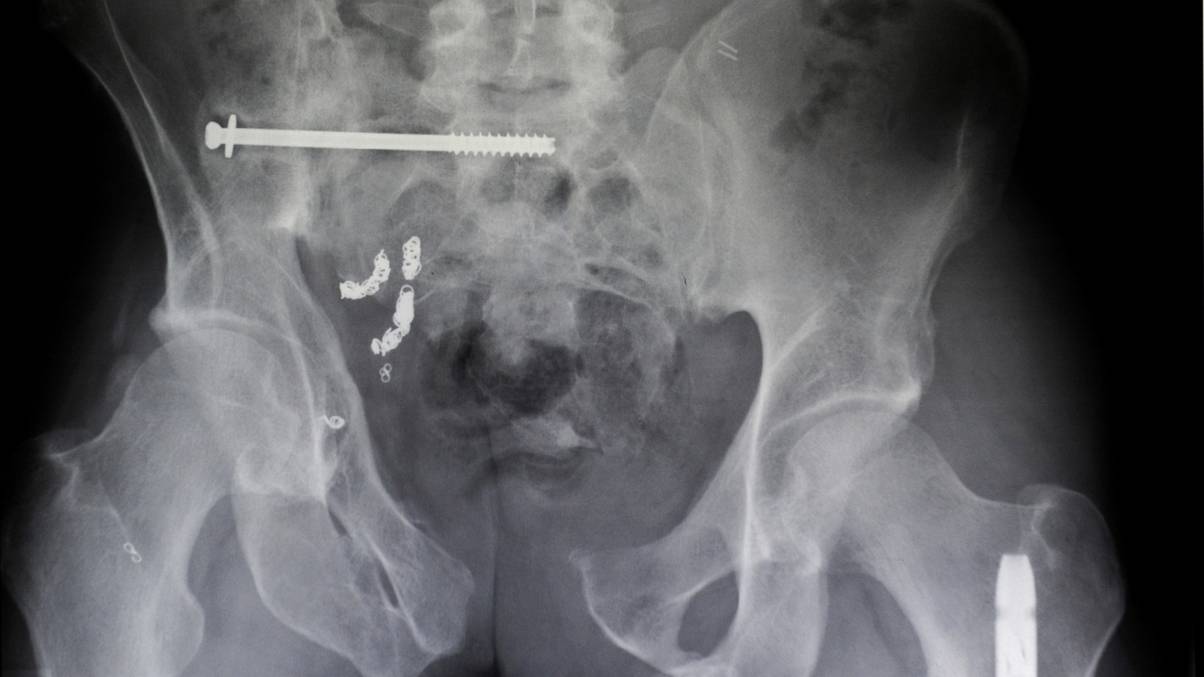

1. Screws and nails